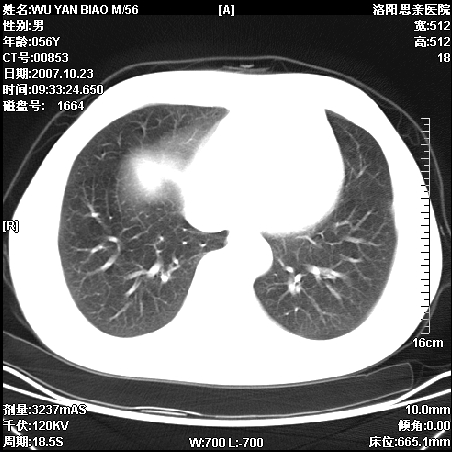

标题: CT10160:M56Y,体检发现,病人无不适,病人随访中 [打印本页]

标题: CT10160:M56Y,体检发现,病人无不适,病人随访中

后上纵隔占位,与肺交界清,宽基底附着脊柱,密度均匀,局部骨质无明确改变.

考虑;神经源性肿瘤,---起源交感n链?,不除外肠源性囊肿.

与纵隔关系密切,密度均匀。只能考虑:后纵隔神经原性肿瘤!

1、病灶在后纵隔脊柱旁沟内,此处是神经原性肿瘤的好发部位

2、病灶边缘光滑整齐,更说明病灶来于纵隔,由于有胸膜的包裹所以才导致这么光滑的边缘

3、病灶内的密度均匀